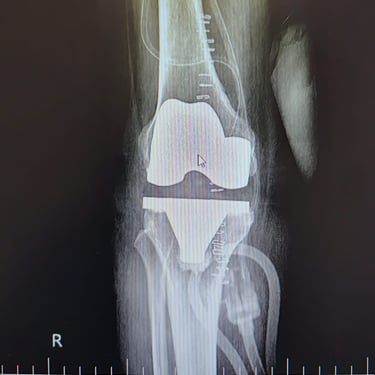

Total knee replacement and partial knee replacement

Gallery